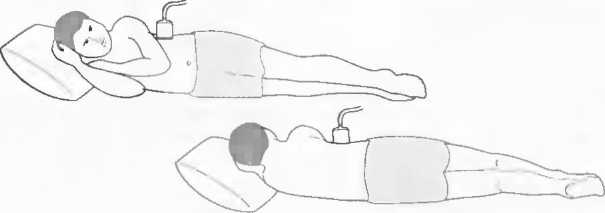

1. Подготовка

Пациент не должен пить и есть в течение 8 ч перед исследованием. Если жидкость необходима для предотвращения дегидратации, можно давать пациенту только воду. При острой симптоматике исследование можно проводить без подготовки. Детям, если позволяют клинические условия, пища и вода не даются в течение 3 ч до исследования.

При более углубленном исследовании, если нет клинических противопоказаний, может быть полезным дополнительный прием воды, особенно при исследовании поджелудочной железы, нижних отделов живота и таза.